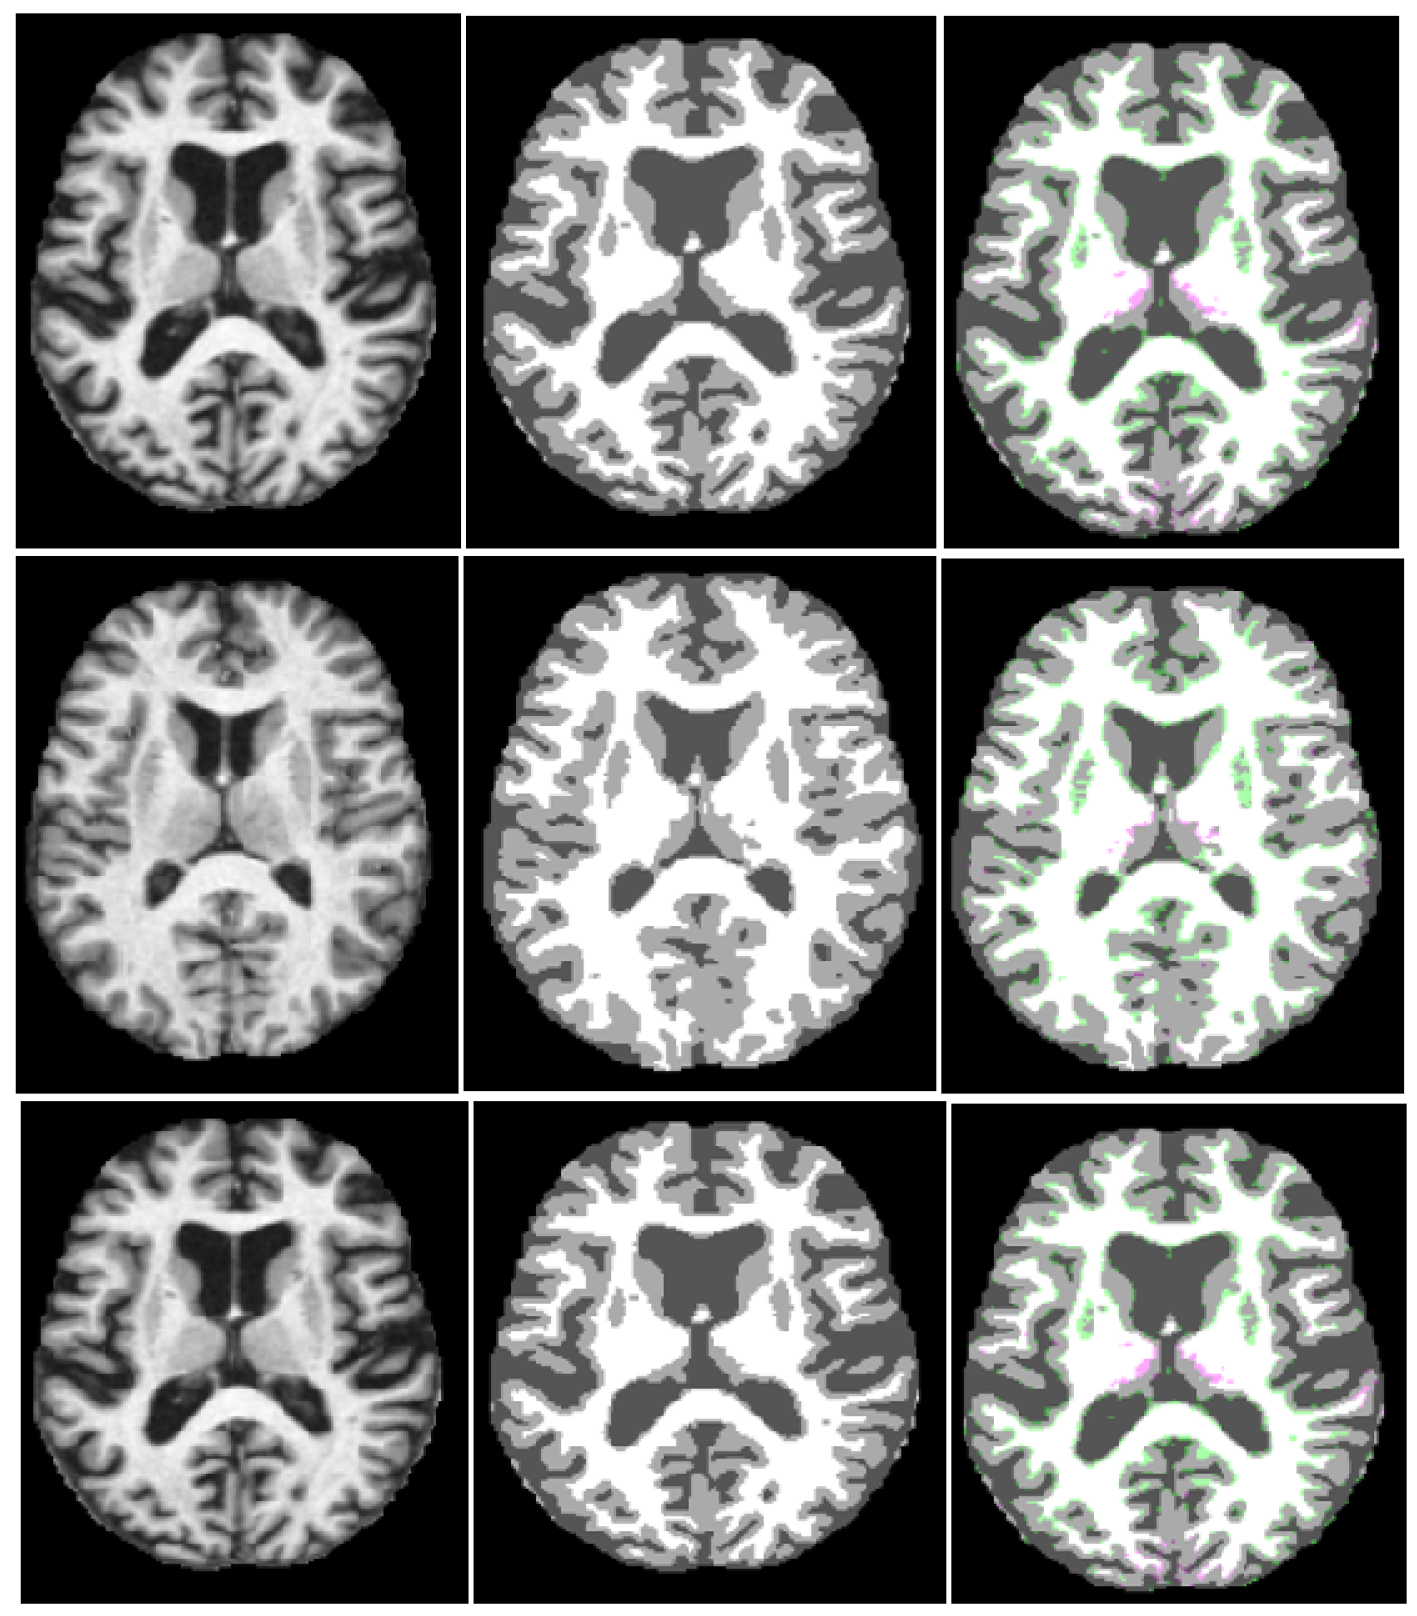

3.4.1. Results on OASIS Dataset

3.4.2. Results on IBSR18 Dataset